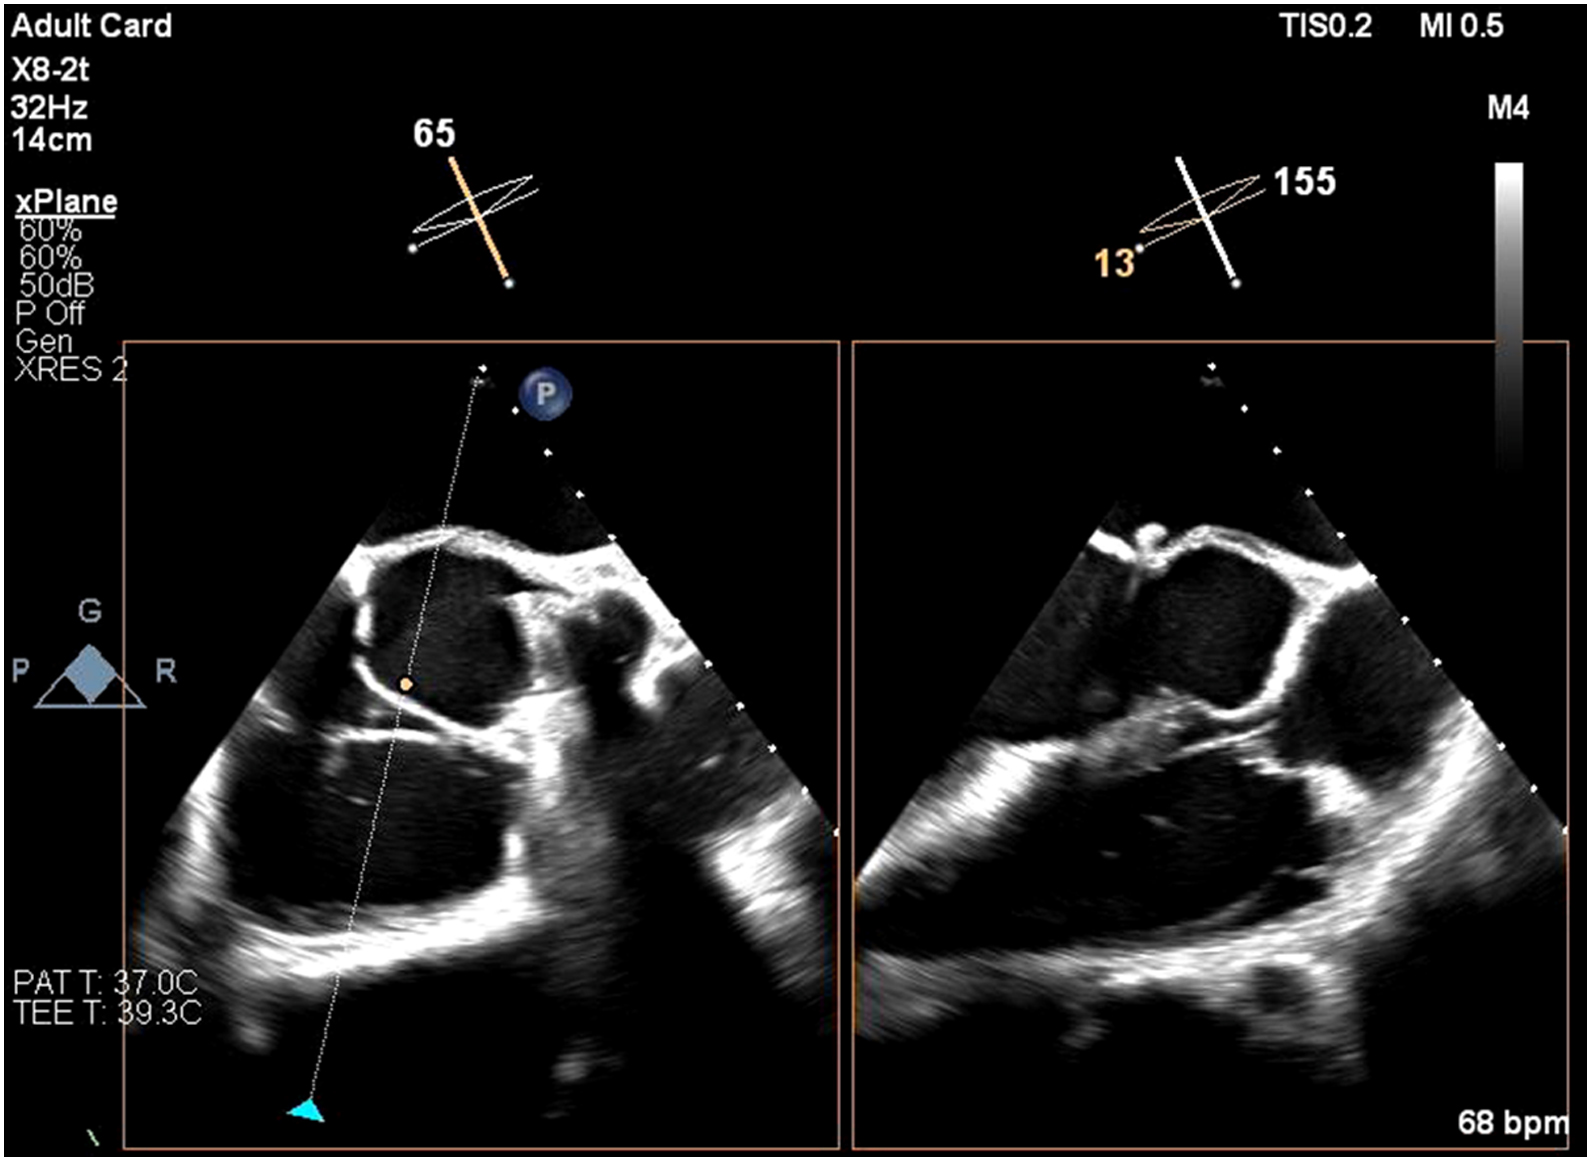

Echocardiogram showed impaired LV systolic function, global wall hypokinesia, normal prosthetic aortic valve function with mild paravalvular leakage and bulging of aortomitral intervalvular fibrosa, suspected

Aortomitral intervalvular fibrosa aneurysm.

CT cardiac revealed pseudoaneurysm of the aortomitral intervalvular fibrosa with laminated thrombus with no LAA thrombus visualized.